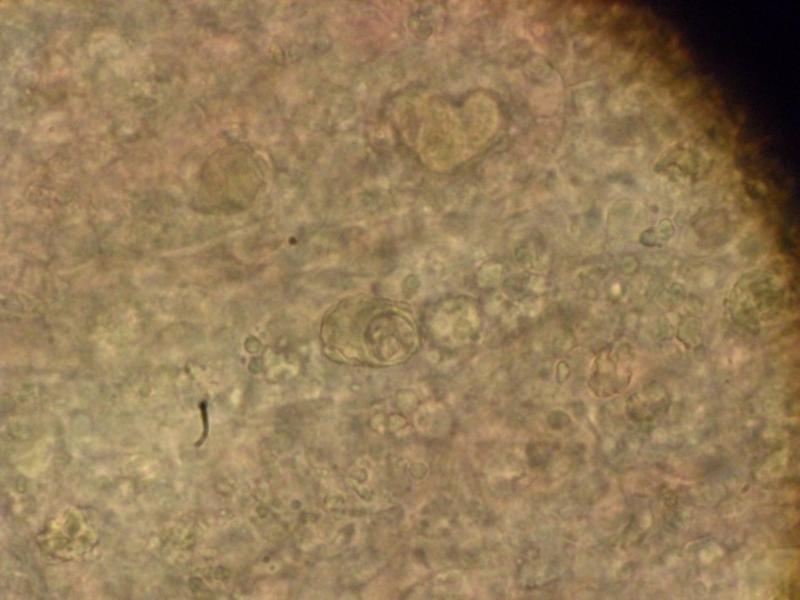

Следующим нашим объектом будет КОКЦИДИЯ вызывающая КОКЦИДИОЗНЫЙ ЭНТЕРИТ . многие любители золотых рыбок видели её работу (в основном азиатских да и местных то-же) , рыбка "усыхает" , остается только голова и брюхо "выпуклое во внутрь" с тонкой спиной .Живет в кишечнике больной рыбы и через экскременты (светлые- белесые, длинные нити, здесь их то-же легко увидеть в микроскоп) заражает всех остальных.Болеют все формы золотых и карпы .Может сохранять жизнеспособность до 7 лет в ГРУНТЕ, КОРНЯХ РАСТЕНИЙ (И СВОИХ И КУПЛЕННЫХ) , В ЩЕЛЯХ ДЕКОРАЦИЙ И ЭЛЕМЕНТАХ ФИЛЬТРОВ, В ЩЕЛЯХ СИЛИКОНА .При покупке больную рыбу всегда видно, перед поселением в аквариум необходим АКТИВНЫЙ КАРАНТИН , карантинный аквариум потом моется с БЕЛИЗНОЙ. На фото всегда хорошо видны округлые шарики как-бы с дольками внутри . http://pisciculture.ru/action/disease?id=194 Лечится легко, выводится из аквариума -- долго. Чеснок - раз в неделю дает положительный результат . http://www.aquaforum.ua/attachment.p...1&d=1364644072 http://www.aquaforum.ua/attachment.p...1&d=1364644205 http://www.aquaforum.ua/attachment.p...1&d=1364644298